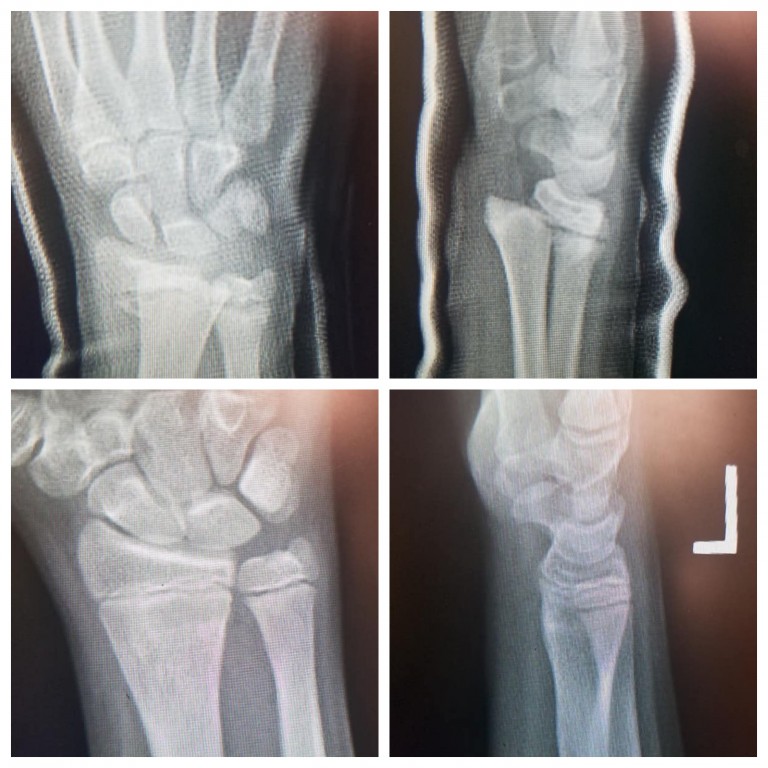

Distal End Radius Pediatric . Distal radius fractures demonstrate significant potential for remodeling of angular deformity and bayonet apposition, even in. When treating a distal radius fracture, the goal is to achieve a normal range of motion and alignment, including wrist flexion and extension and forearm pronation and supination. A recent survey suggests that most pediatric orthopedic society of north america members would perform sedated reduction of 100% displaced distal radius fractures in children under age 10 years. Diagnosis is made clinically and radiographically with orthogonal radiographs of. Distal radius fractures are the most common site of pediatric forearm fractures and generally occur as a result of a fall on an outstretched hand with the wrist extended. This observational study investigated the incidence of distal radius fractures in children, to determine whether the rate is rising, the effect of. Distal radius fractures are the most common orthopaedic injury and generally result from fall on an outstretched hand. Distal radius fractures are among the most common pediatric injuries, affecting thousands of children each year.

Distal radius fractures are among the most common pediatric injuries, affecting thousands of children each year. Diagnosis is made clinically and radiographically with orthogonal radiographs of. This observational study investigated the incidence of distal radius fractures in children, to determine whether the rate is rising, the effect of. When treating a distal radius fracture, the goal is to achieve a normal range of motion and alignment, including wrist flexion and extension and forearm pronation and supination. Distal radius fractures are the most common orthopaedic injury and generally result from fall on an outstretched hand. A recent survey suggests that most pediatric orthopedic society of north america members would perform sedated reduction of 100% displaced distal radius fractures in children under age 10 years. Distal radius fractures are the most common site of pediatric forearm fractures and generally occur as a result of a fall on an outstretched hand with the wrist extended. Distal radius fractures demonstrate significant potential for remodeling of angular deformity and bayonet apposition, even in.

Distal End Radius Pediatric Diagnosis is made clinically and radiographically with orthogonal radiographs of. Distal radius fractures are among the most common pediatric injuries, affecting thousands of children each year. Distal radius fractures are the most common orthopaedic injury and generally result from fall on an outstretched hand. A recent survey suggests that most pediatric orthopedic society of north america members would perform sedated reduction of 100% displaced distal radius fractures in children under age 10 years. Distal radius fractures demonstrate significant potential for remodeling of angular deformity and bayonet apposition, even in. When treating a distal radius fracture, the goal is to achieve a normal range of motion and alignment, including wrist flexion and extension and forearm pronation and supination. Diagnosis is made clinically and radiographically with orthogonal radiographs of. This observational study investigated the incidence of distal radius fractures in children, to determine whether the rate is rising, the effect of. Distal radius fractures are the most common site of pediatric forearm fractures and generally occur as a result of a fall on an outstretched hand with the wrist extended.